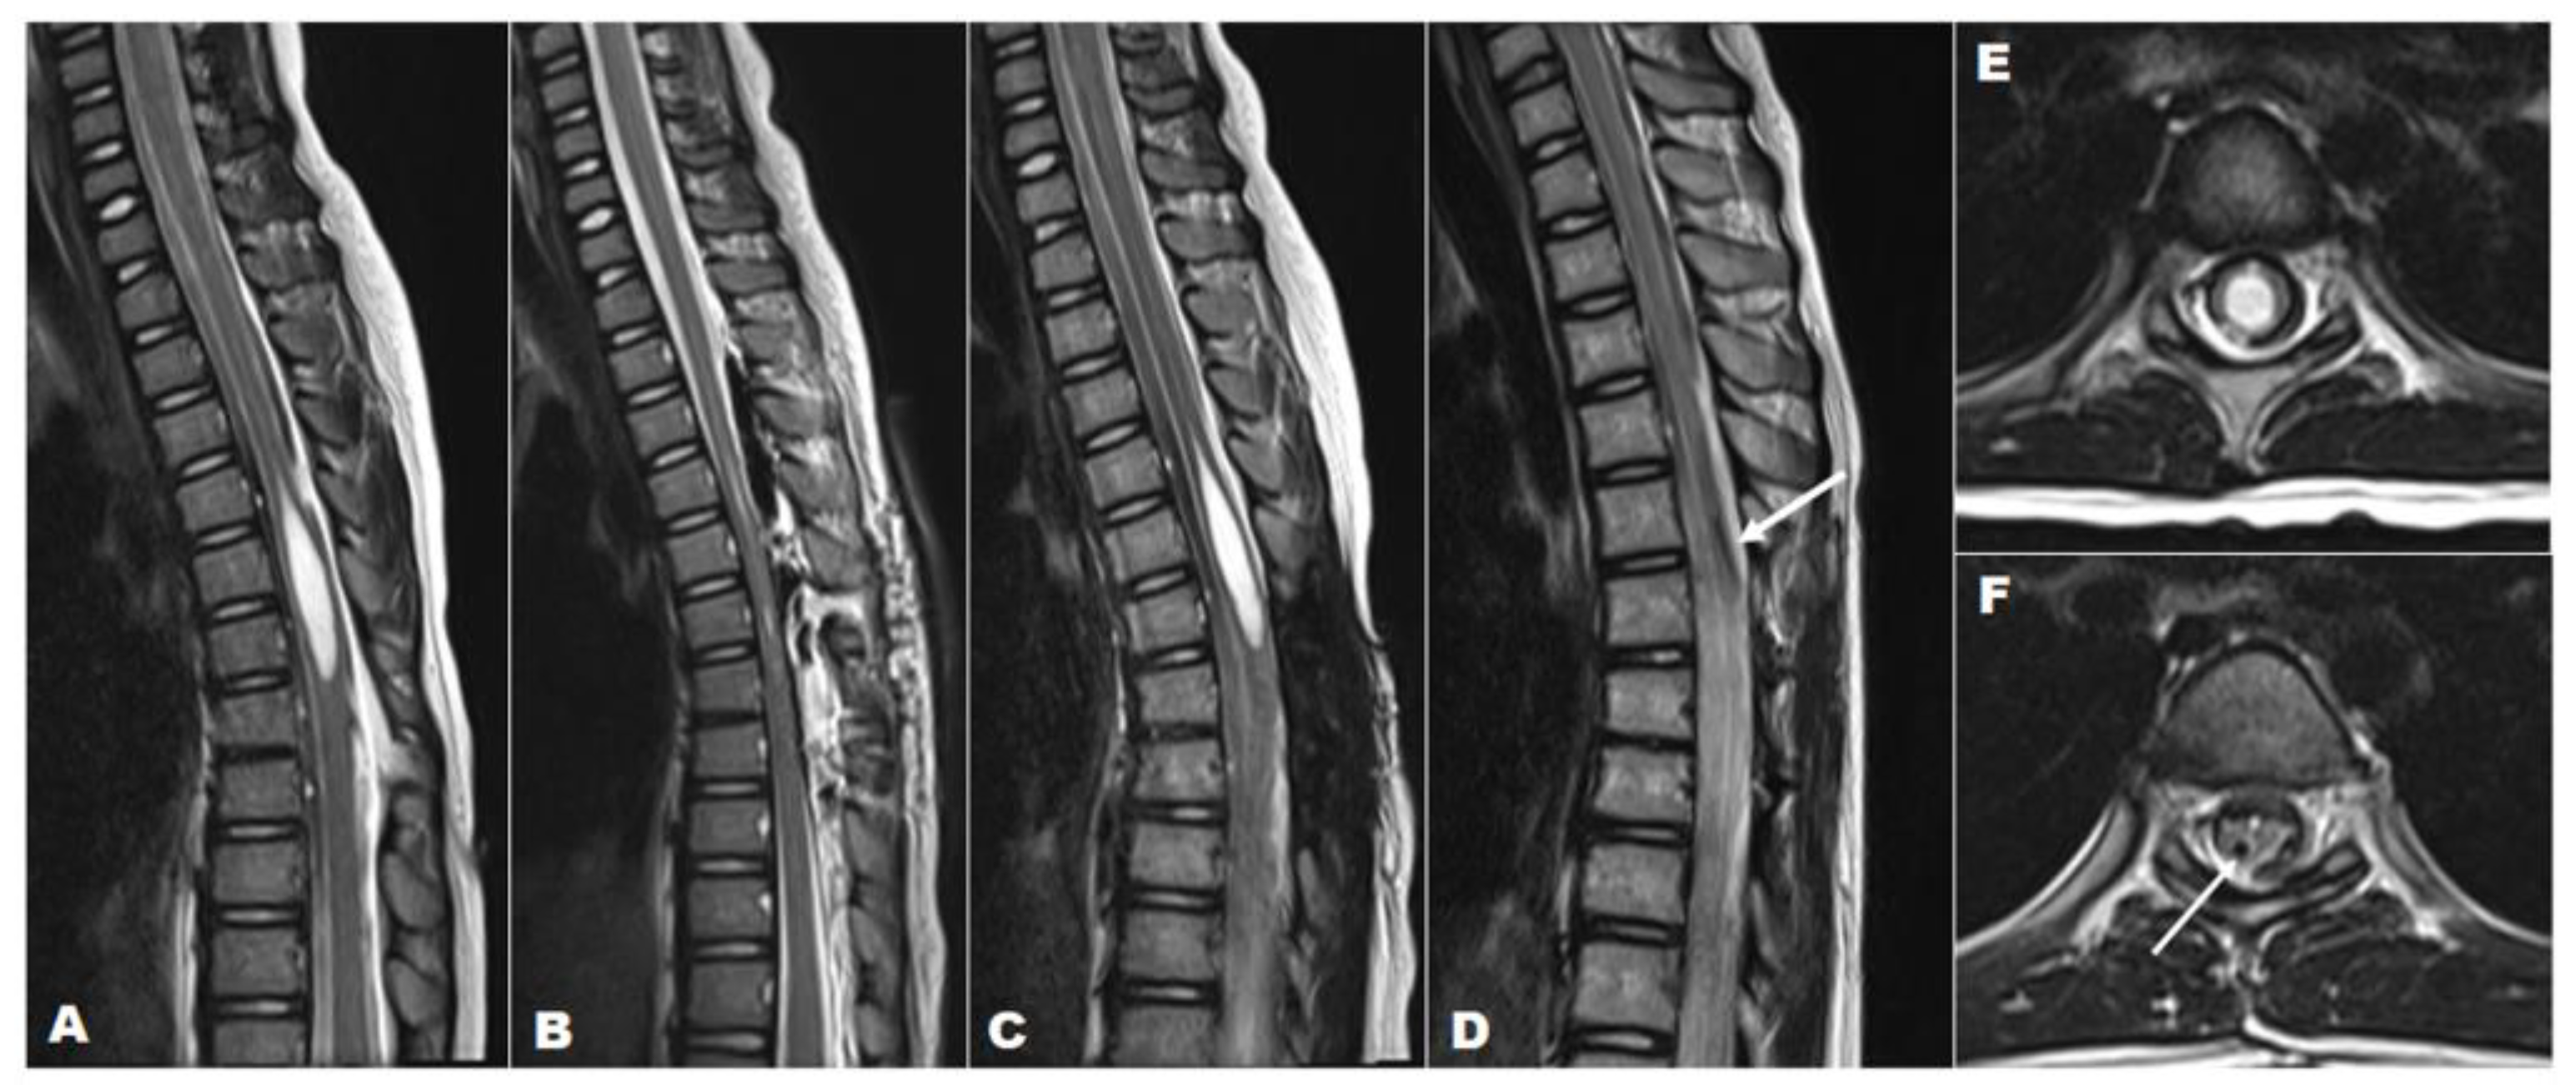

This illustrative case aims to demonstrate the application of a syringo-pleural shunt with a reservoir valve implant for the treatment of syringomyelia associated with TCS. A 7-year-old female was referred to our tertiary care hospital for a skin tag on her back and gait abnormalities. On history taking, it was noted that she had had an asymptomatic skin tag on her thoracic spine (Figure 4) since birth. However, it had become symptomatic, causing shock-like leg tingling sensations and episodic paraparesis when touched or pulled. A preoperative MRI revealed syringomyelia extending from T4 to T6 (SI > 0.8), which was associated with a dermal sinus tract through spina bifida at T7-8 (Figure 4). Initially, she underwent an osteoplastic laminotomy of T6–T8 with complete resection and reconstruction of the dermal sinus tract, along with a midline myelotomy and syrinx drainage at T6 (Figure 4). Following the surgery, an immediate postoperative MRI showed complete resolution of the syrinx; however, a recurrence of the syrinx, at the same size as preoperative, was noted in a follow-up MRI performed 7 months postoperatively. Finally, a syringo-pleural shunt using a reservoir valve was performed for the recurrent large syrinx. As a result, the patient exhibited both clinical and radiographic improvement and remained well during a follow-up period of 6 years.

Figure 4. A 7-year-old girl with a large loculated syringomyelia, T4–T6, caused by a dermal sinus tract. Serial sagittal MRI images (T2-weighted) demonstrate (A) the preoperative syrinx (T4–T6) with TCS, (B) the complete syrinx resolution immediately post-untethering and simple drainage, (C) the syrinx recurrence at the previous location at 6 months post-untethering with almost the same size as the preoperative syrinx, and (D) the absence of the syrinx and the proximal catheter that was previously implanted (white arrow) at follow-up after 6 years post-shunt surgery. T2-weighted axial MRI indicating (E) the preoperative syrinx (SI > 0.8) and (F) the complete resolution of the syrinx and the proximal catheter (white arrow) at final follow-up 6 years after shunt surgery.